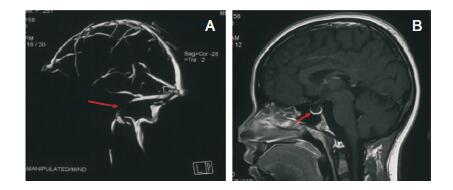

血常规:白细胞10.06×109/L、血小板444×109/L。生化:谷丙转氨酶 241 U/L、谷草转氨酶 114 U/L。血沉:20 mm/H。自身免疫抗体:抗心磷脂抗体 15.9 RU/ml。水通道蛋白-4抗体:(-)。 眼底:双眼视盘水肿。眼压:右眼16 mmHg、左眼15 mmHg。 谱域光学相干断层扫描(spectral domain-Optical coherence tomography,SD-OCT)测眼底视神经纤维层(retinal nerve fiber layer,RNFL)厚度:右眼264 μm、左眼219 μm。腰椎穿刺:脑脊液压力410 mmH2O。 脑脊液常规、生化:总蛋白 1.04 g/L;免疫、病毒、细菌未见异常。磁共振静脉血管成像(magnetic resonance venography,MRV):左侧乙状窦狭窄,血栓形成可能(图 1A)。头颅磁共振成像(magnetic resonance imagination,MRI):可见空蝶鞍(图 1B)。

| 图 1 头颅MRV和MRI影像学检查。A:头颅MRV提示左侧乙状窦狭窄,箭头所示左侧乙状窦部分未显影;B:头颅MRI失状位可见空蝶鞍(箭头所示)。 |